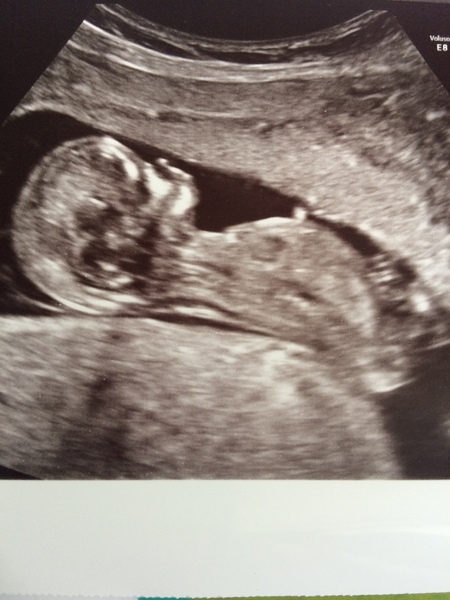

Hello all, checked no in after my dating scan today. I am 13+1, as the measurements have confirmed.

They found a heartbeat, but couldn't get the baby moving! It was sleeping on its side

I had to go to the courtyard and jump around for ten minutes (not looking weird at all!), then they rescanned: this time, the baby had turned onto its back, but was still asleep... It woke up eventually to make some jerky whole-body movements and to open its mouth a few times.